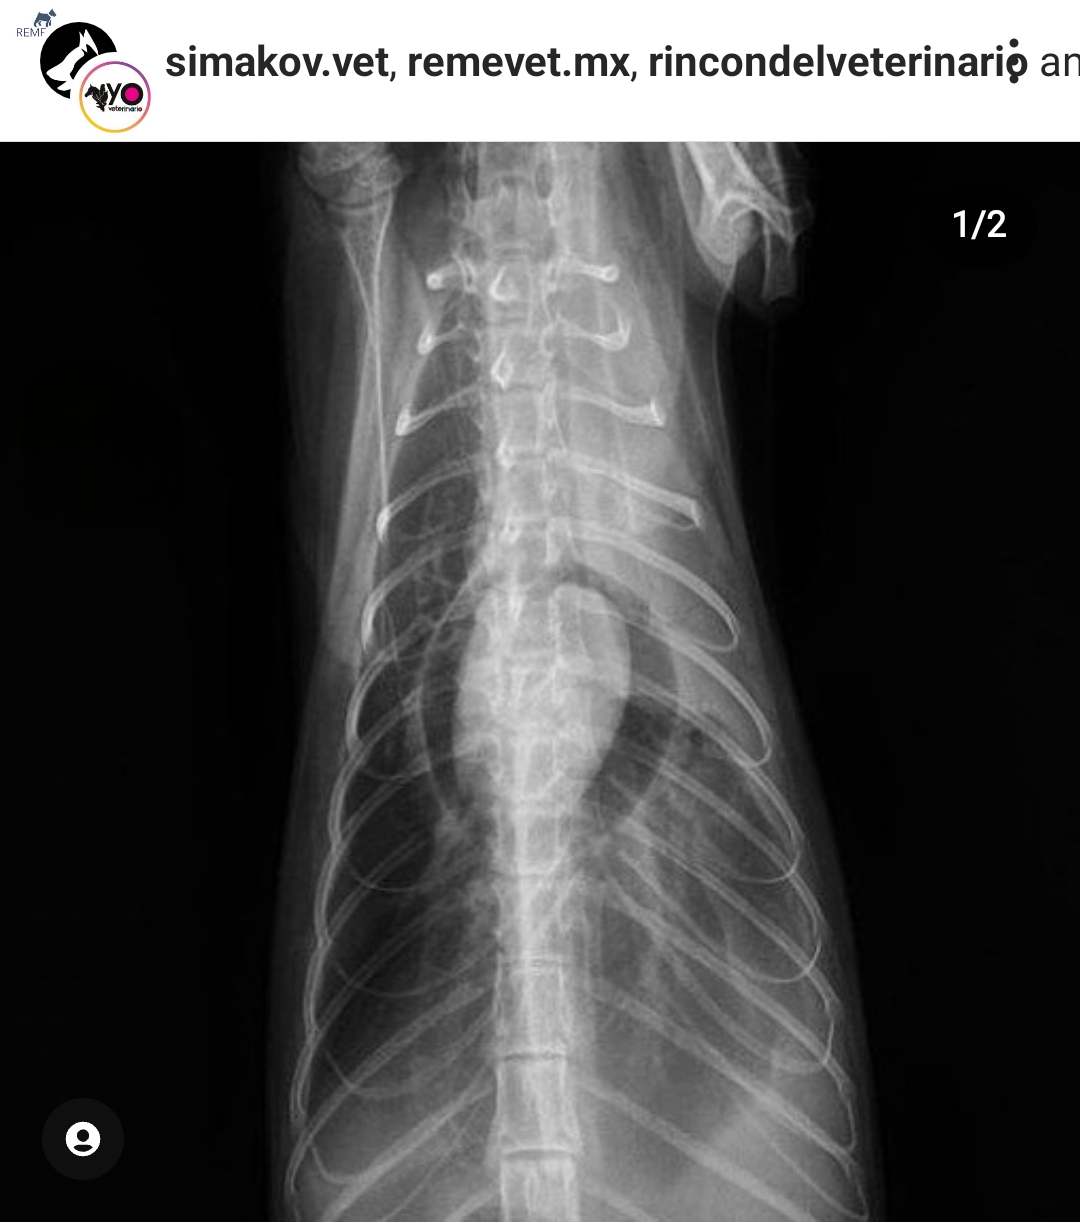

2犬猫胸腔积液和肺水肿的X光片诊断阅读 (1940)

3腹背位(VD)胸片阅读 (1796)